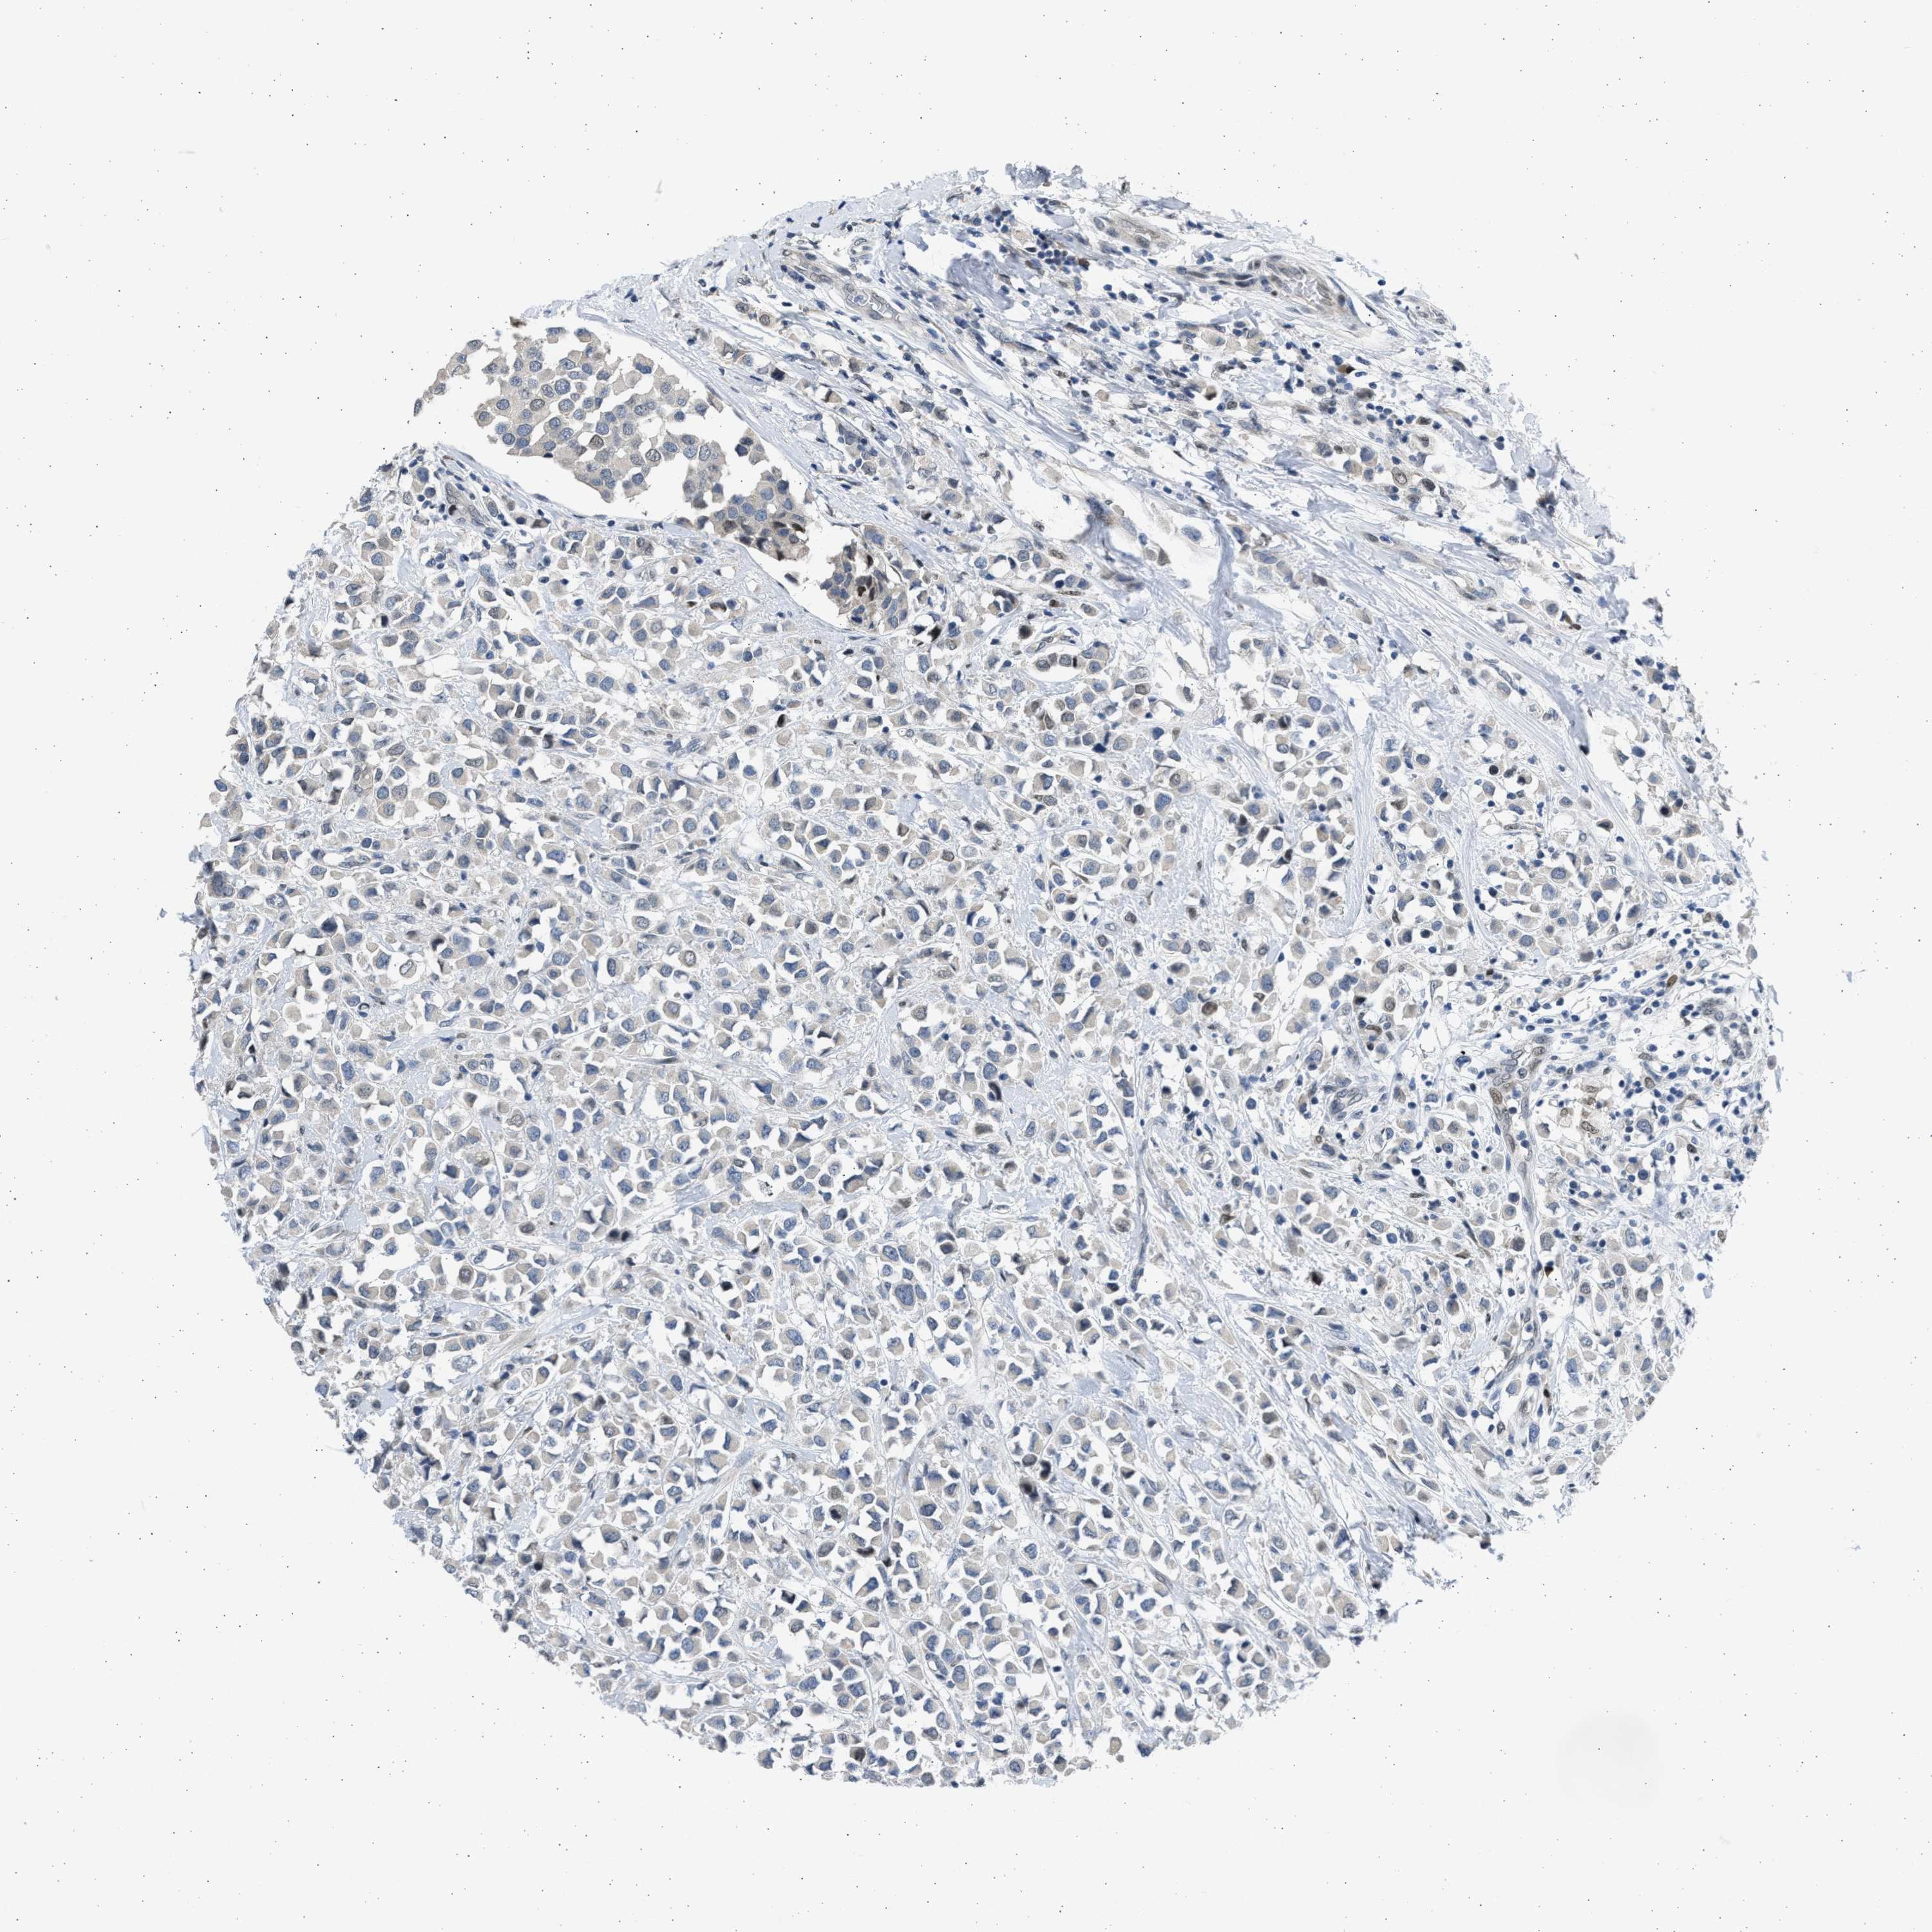

CANCER BREAST CANCER Show tissue menu

BRCA TCGA BRCA VALIDATION PROTEIN EXPRESSION